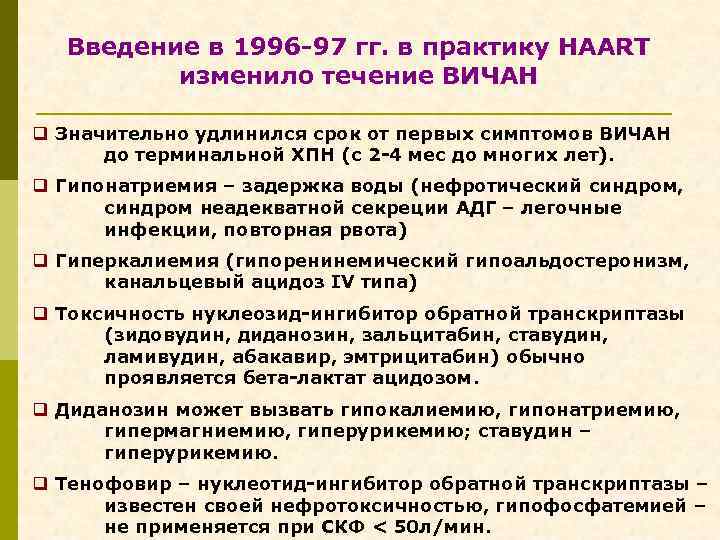

Введение в 1996 -97 гг. в практику HAART изменило течение ВИЧАН q Значительно удлинился срок от первых симптомов ВИЧАН до терминальной ХПН (с 2 -4 мес до многих лет). q Гипонатриемия – задержка воды (нефротический синдром, синдром неадекватной секреции АДГ – легочные инфекции, повторная рвота) q Гиперкалиемия (гипоренинемический гипоальдостеронизм, канальцевый ацидоз IV типа) q Токсичность нуклеозид-ингибитор обратной транскриптазы (зидовудин, диданозин, зальцитабин, ставудин, ламивудин, абакавир, эмтрицитабин) обычно проявляется бета-лактат ацидозом. q Диданозин может вызвать гипокалиемию, гипонатриемию, гипермагниемию, гиперурикемию; ставудин – гиперурикемию. q Тенофовир – нуклеотид-ингибитор обратной транскриптазы – известен своей нефротоксичностью, гипофосфатемией – не применяется при СКФ < 50 л/мин.

Введение в 1996 -97 гг. в практику HAART изменило течение ВИЧАН q Все ингибиторы протеазы (индинавир и другие) способны причинить нефролитиаз. Классический вариант – кристаллурия, которая развивается независимо от функции почек, однако проходит после отмены препарата. Нефротоксичность препаратов при лечении оппортунистических инфекций Препарат Бактрим Нарушение К+, Na+ Амфотерицин К+, Са++, Mg++ Пентамидин К+ Интраконазол ОПН K+, Na+ Фоскарнет Na+, K+ Na+ Mg++ ОПН / Ca++, PO 4 --, ОПН